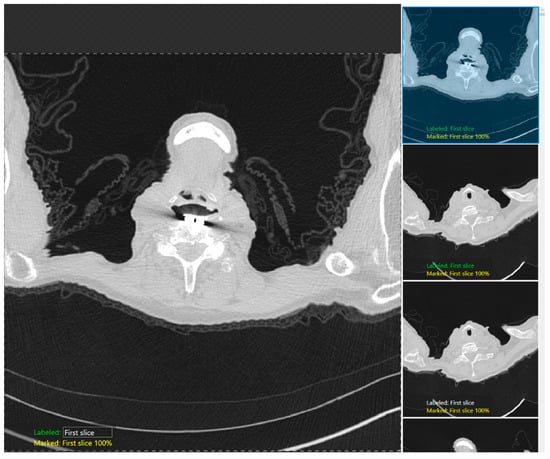

2.5. Training

We used the classification tool to classify three labeled CT images for each anatomical landmark at the lung apices and bases and trained two different DL models on the DL building platform, one (R3-5) each for lung apices and bases. Figure 2 shows the snippet of the software GUI used for classification. DICOM (Digital Imaging and Communications in Medicine) (R3-3) format CT images were first deidentified, uploaded into the software, and then labeled with each category: the first image, just above the apices, and the image with the apices for the apices detection model; the last image, just below the bases, and the image with the bases for the bases identification model). The training set in each model comprised of 70% of the image dataset selected randomly by the software, with the remaining 30% being the test dataset. Each model was cross-validated with a five-fold cross-validation method in which the test and training data were randomized, and the performance was reassessed.

Figure 2. A snapshot of the Green Tool of the DL software used for classification of the anatomic locations at the lung apex.